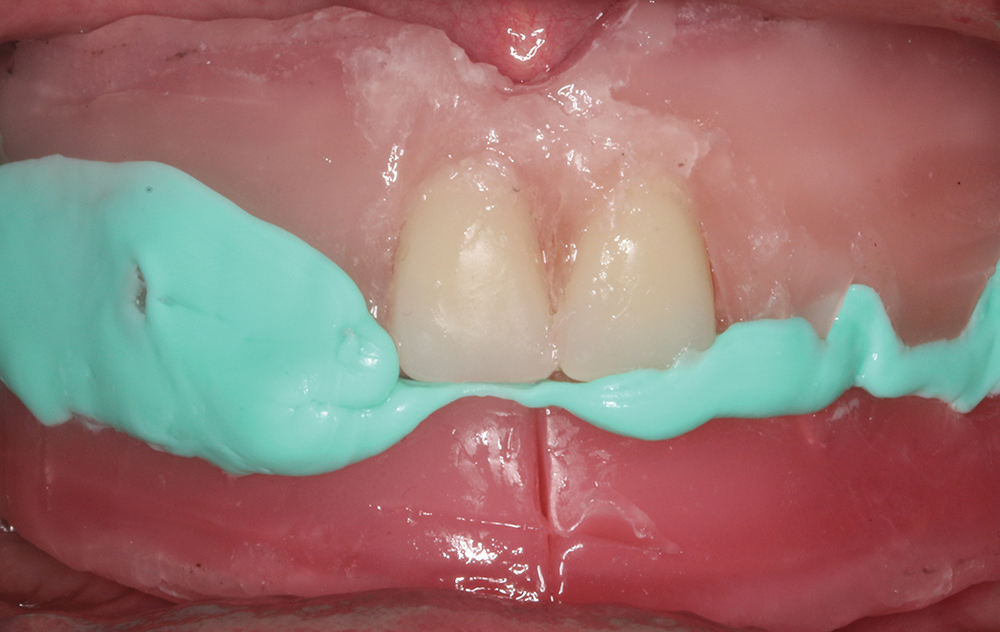

In the standard protocol for the Locator Overdenture, the Locator housings are processed into the overdenture by the dental lab. However, some doctors may prefer to pick up the Locator housings intraorally. The following presentation, courtesy of Len Conner, CDT, director of education and clinical affairs at Zest Dental Solutions, illustrates the straightforward clinical procedure for intraoral pickup.